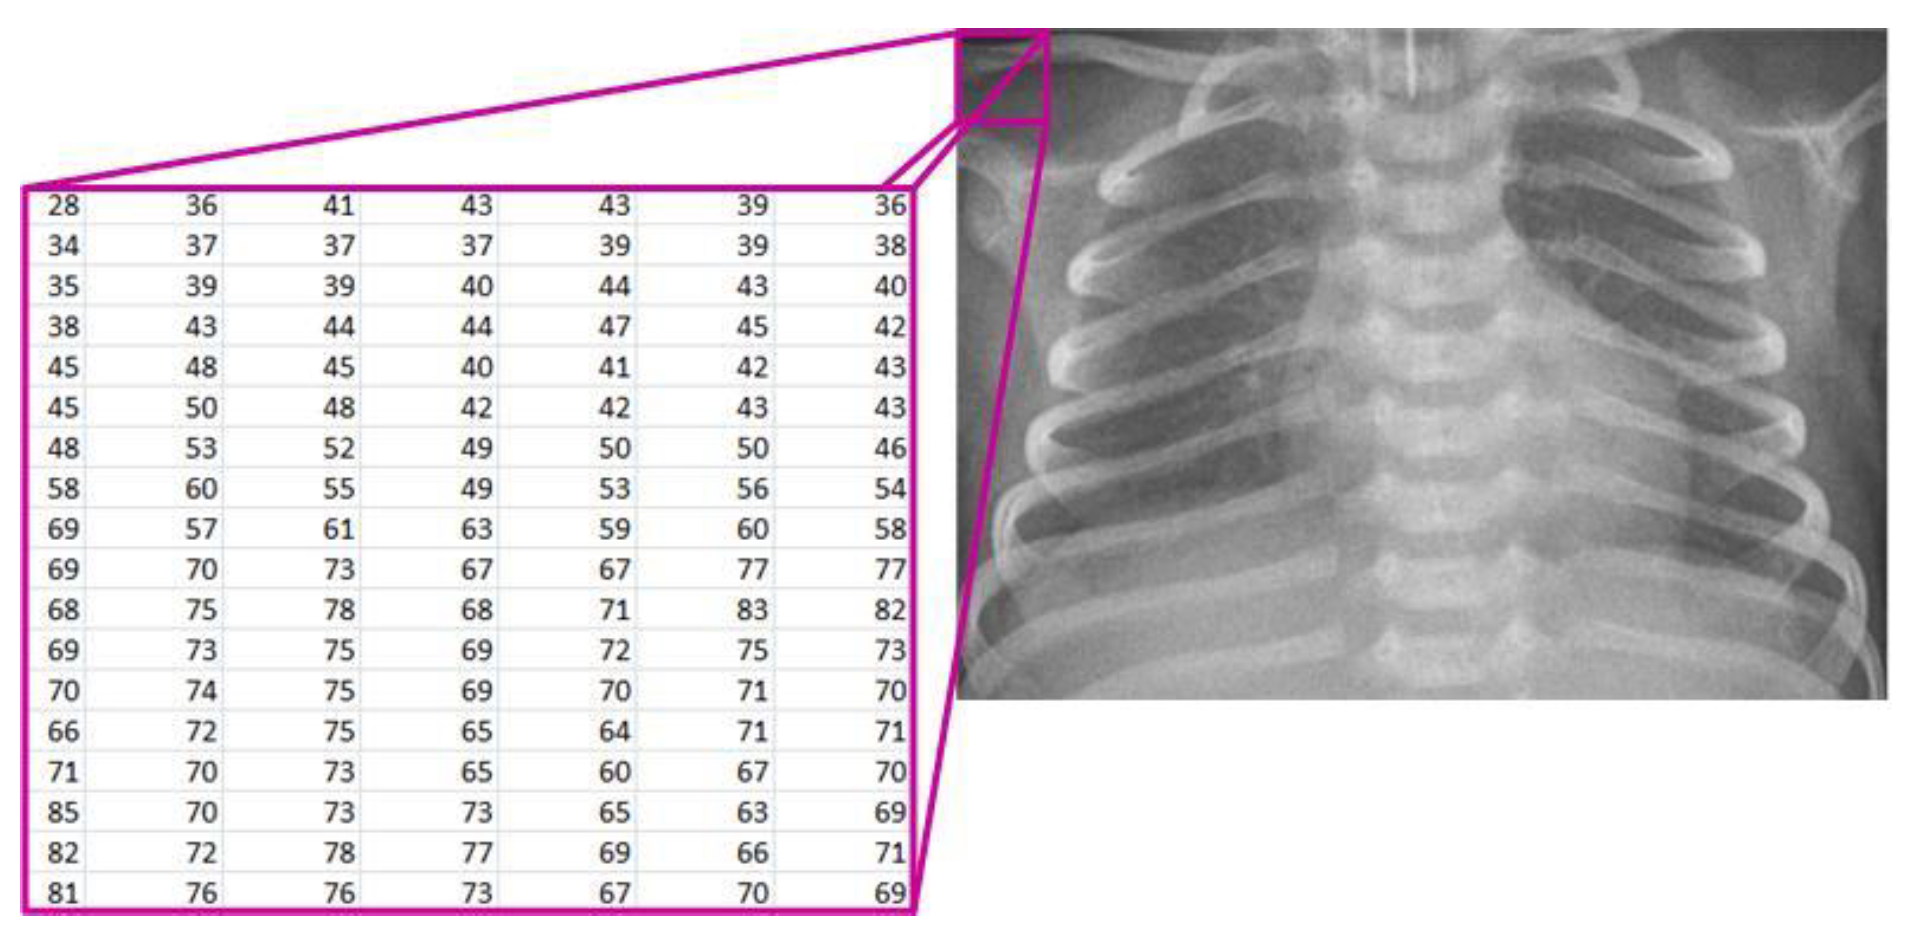

Starting from the image loaded from the corresponding database, it is displayed on the screen and treated mathematically (Figure 2). The image is denoted as [7,19]:

where

Figure 2.

Mathematical representation of the X-ray image.

- R—the set of real numbers;

- M—the number of rows in the image;

- N—the number of columns in the image;

- X(i, j)—the pixel intensity at position (i, j).